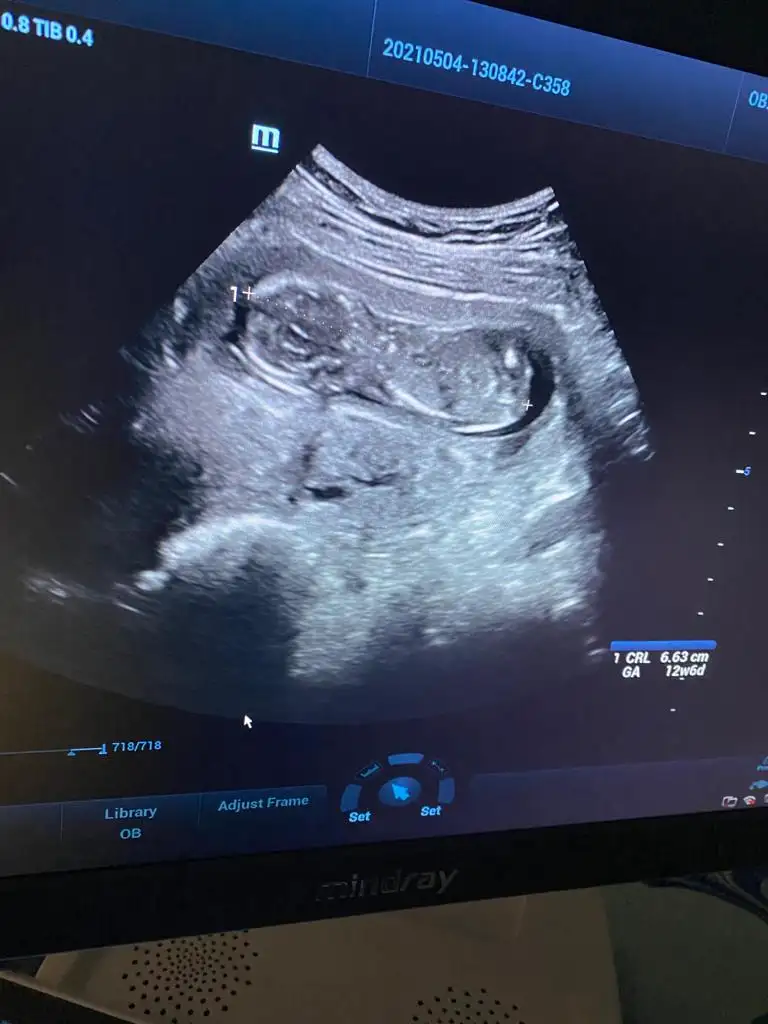

Hiiççç belli olmaz Allah kalbindekini kucağına versin inşallahKızlar hepinize toplu cevap vereyim, 12+6, çıkıntı göremedi, cinsiyet için bişiy demedi ama bu haftada biraz çıkıntı olması gerekmezmiydibüyük. İhtimal kız

Hayırlısı olur canım.allah bilir daha kucuk.ama hakkımızda hayırlısını Allah bilir.saglikla süratle kucağına almak nasip olsun insallahİnşallah dediğiniz gibi olur kızlar ama hiç zannetmiyorum benim 2 kızımada devlette 12 haftada kız dediler değişmedi, bugün özeldeydik renkli renksiz bütün usg lere baktı yarım saat inceledi neredeyse, pozisyonuda uygundu bacak arası boştu ben biile gördüm, ben değişceğini düşünmüyorum kız olduğunu kabullendim hayırlısı böleymiş

Ne tatlı maşallah annesi özlemişim ultrason resmi görmeyi böyle:)...Allah hayırlısını nasip etsin sağlıklısını nasip etsin..Ne olur sağlığın en büyük nimet olduğunu unutma Kız olsun erkek olsun vardır Rabbimin bir bildiği Allah sağ salim kucağına almayı nasip etsin....İnşallah dediğiniz gibi olur kızlar ama hiç zannetmiyorum benim 2 kızımada devlette 12 haftada kız dediler değişmedi, bugün özeldeydik renkli renksiz bütün usg lere baktı yarım saat inceledi neredeyse, pozisyonuda uygundu bacak arası boştu ben biile gördüm, ben değişceğini düşünmüyorum kız olduğunu kabullendim hayırlısı böleymiş

Canım yumurtlama takibi dışında neler yaptınKızlar hepinize toplu cevap vereyim, 12+6, çıkıntı göremedi, cinsiyet için bişiy demedi ama bu haftada biraz çıkıntı olması gerekmezmiydibüyük. İhtimal kız

Ya doktor zaten dediki ben normLde 14 haftdan önce kesinbelli olmadan cinsiyet söylemiyorum, ama ben başından beri aynı doktora gidiyorumya biliyor mevzuları erkek istediğimi upraştıpımı filan bugün o benden meraklıydı yani düşün, o yüzden çok inceledi yani o yine kesin değil amabacak arası boş dedi sadece3 hafta sora gel netkeşir kesin kız diyemem dedi, amaarkadaşım 11 +3 tü cuma günü erkek dedi ona doktor yani ben bugün 12+6 bu kadarda gelişmiş ultrasyonda bide öle yakınlaştırdıki o demeden ben gördüm hemen dedim oğlan olaydı en azından bi ufak çıkıntı olurdu diye, çünkü bacak arasını net gördük, benim için mucize öyle birşey olmayacak değişmiyecekte yinede inş diyeyimCanım arkadaşıma özelde baya iyi bı doktor 15. Haftada kız dedi.bugun 16 haftalık aynı doktor bı bakmis pipiyi saklamış erkekmis.tabi ki her zaman hayırlısını istiyoruz ama hiçte belli olmuyor.